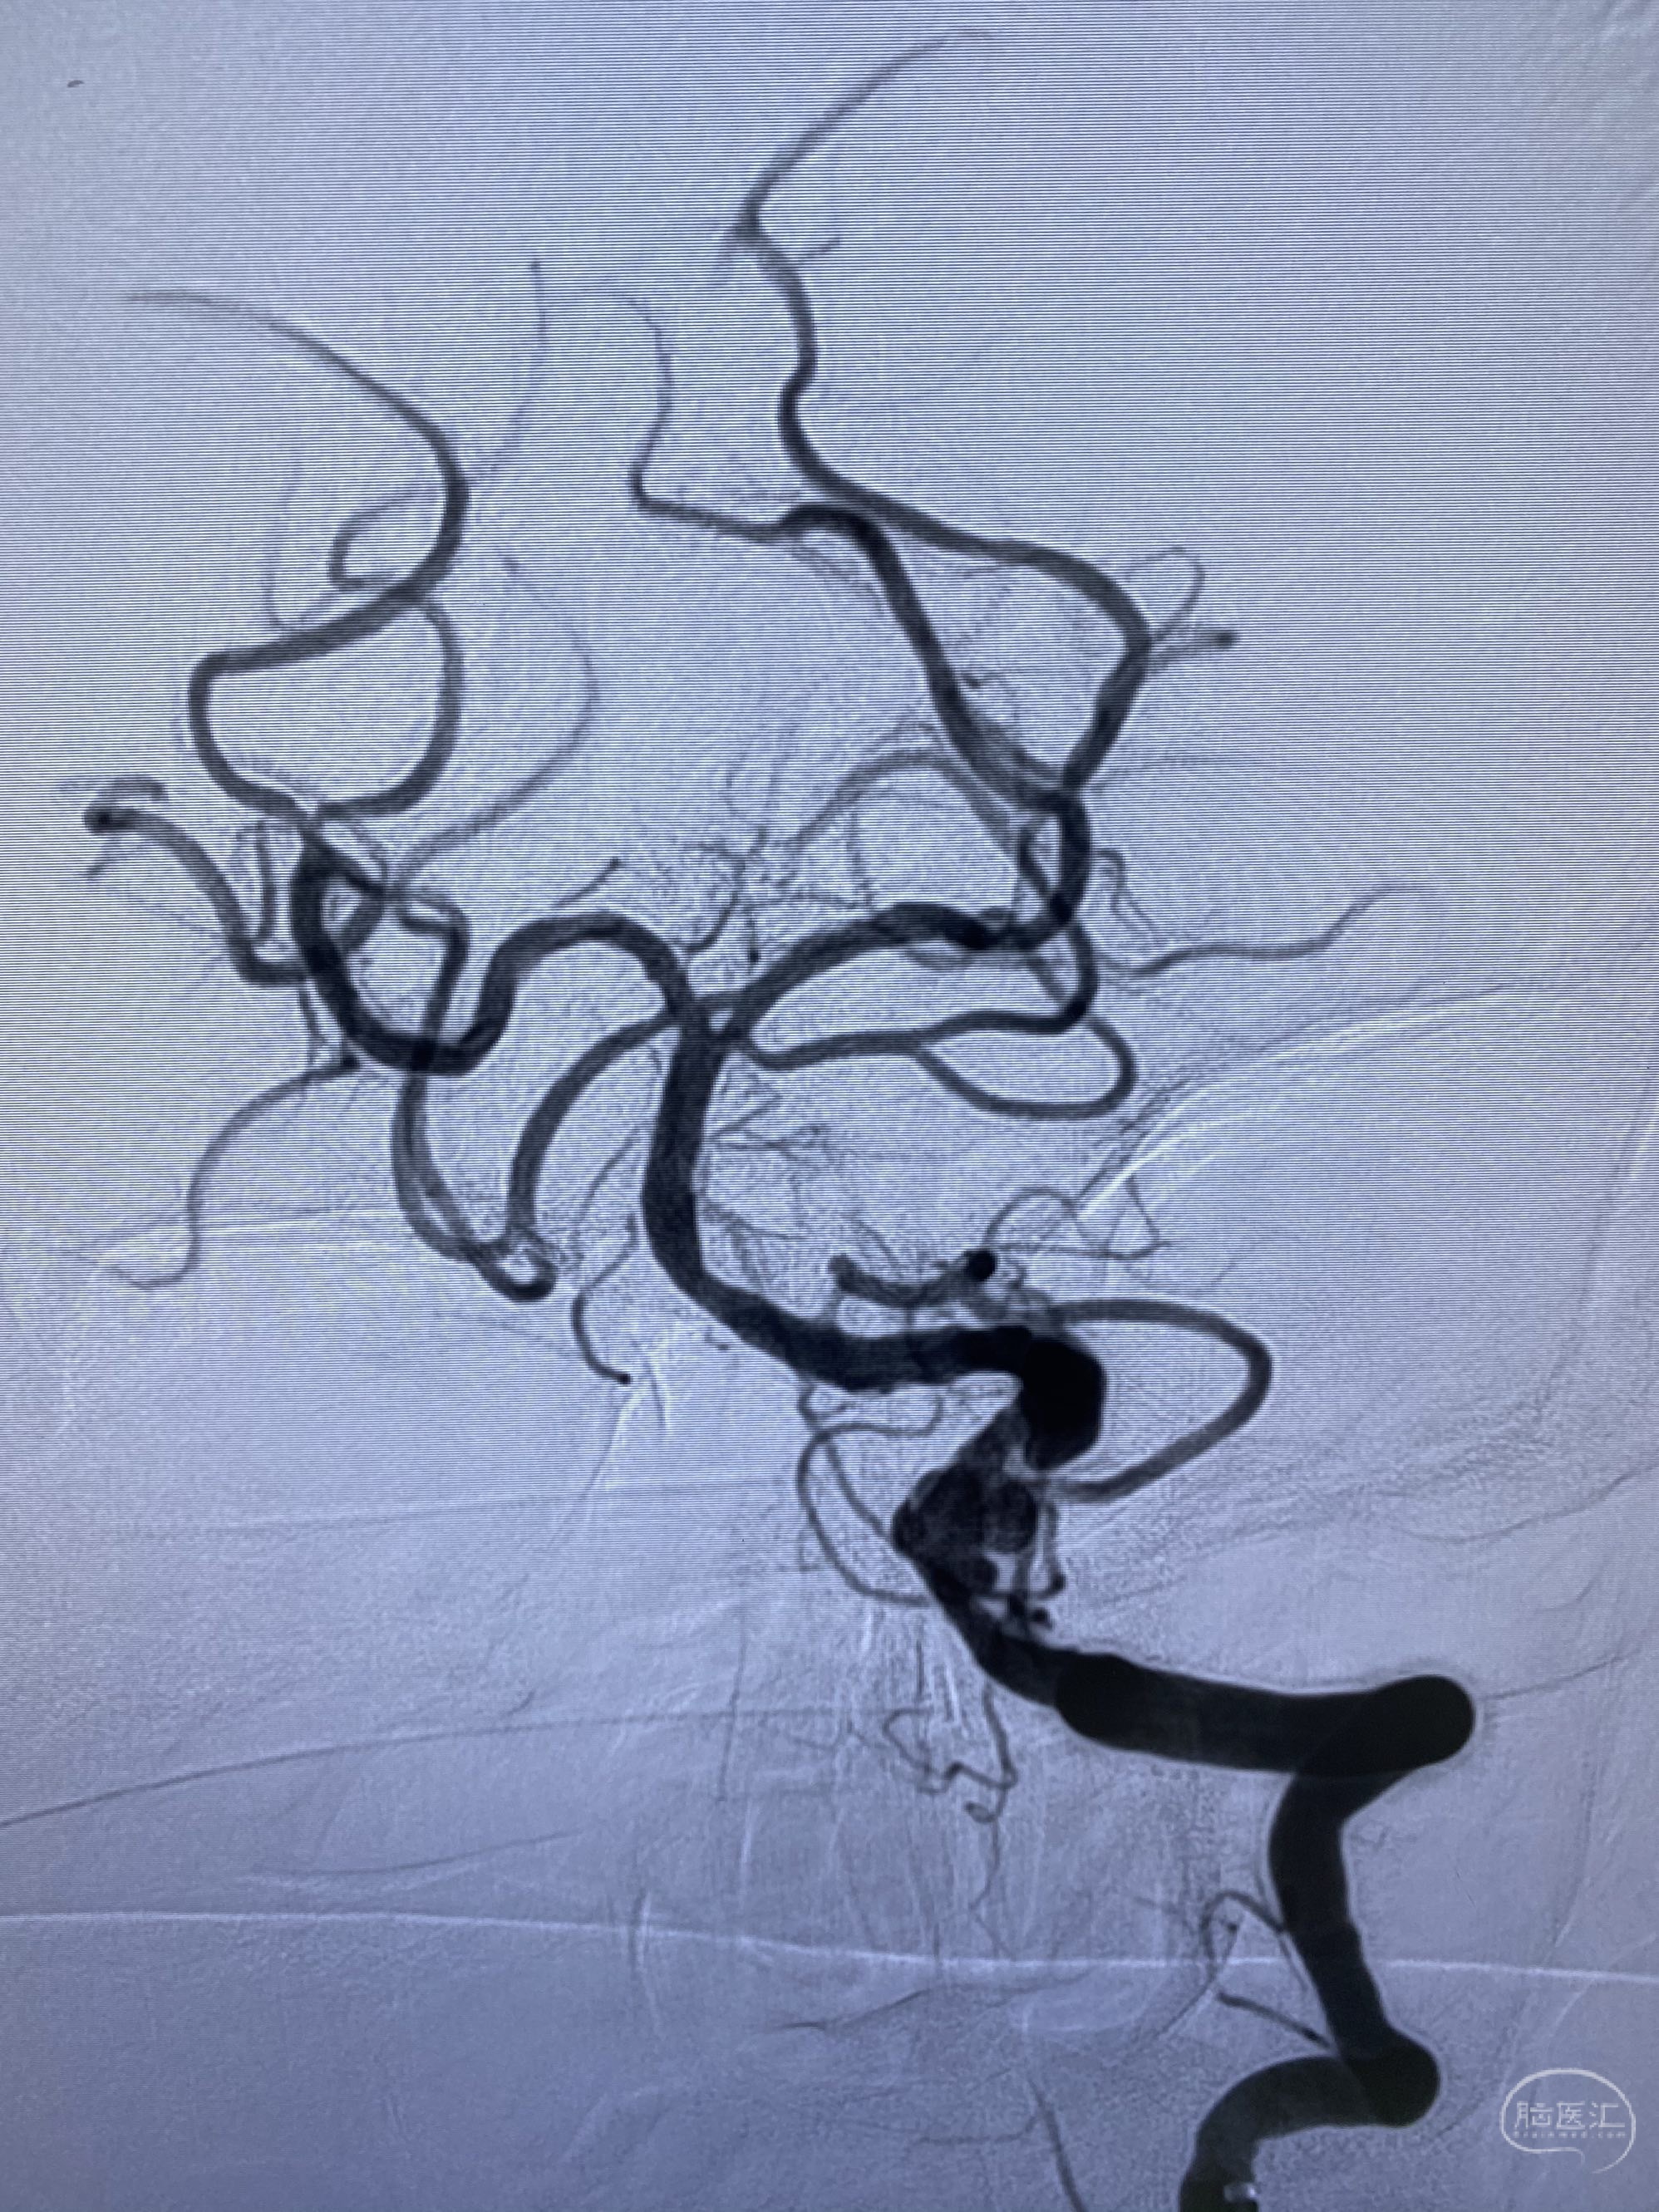

椎动脉颅内段多发夹层动脉瘤伴载瘤动脉狭窄pipeline flex植入

今日手术,TJG,M62Y,一期左侧颈动脉狭窄支架植入,二期椎动脉V4段多发夹层动脉瘤伴狭窄,常规支架辅助栓塞方法复杂又危险,血流导向装置植入快捷又安全。南阳市中心医院神经内科脑血管病介入团队pipeline flexFD植入两人导师资格。